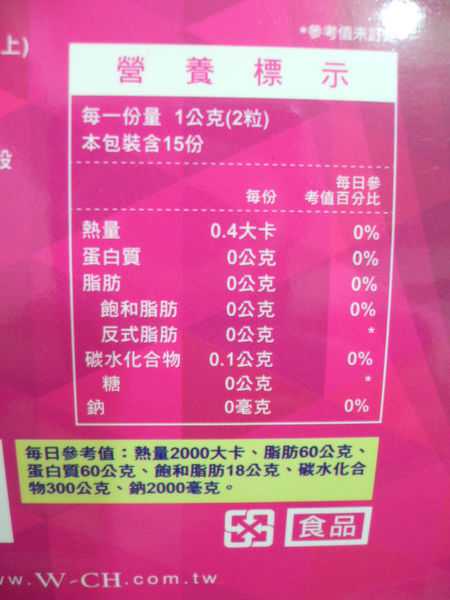

Supercut塑魔纖立塑膠囊的成分有:瓜拿那萃取粉、肉桂萃取粉、辣椒萃取物(唐辛子)、吡啶甲酸鉻、番瀉葉粉末、玉米澱粉、氧化鎂、二氧化矽。

食用方式:早晚餐前30分鐘各1粒,每日不超過2粒。(多食無益)

番瀉葉萃取物每日食用限量為12mg以下,

番瀉葉萃取物每日食用限量為12mg以下,